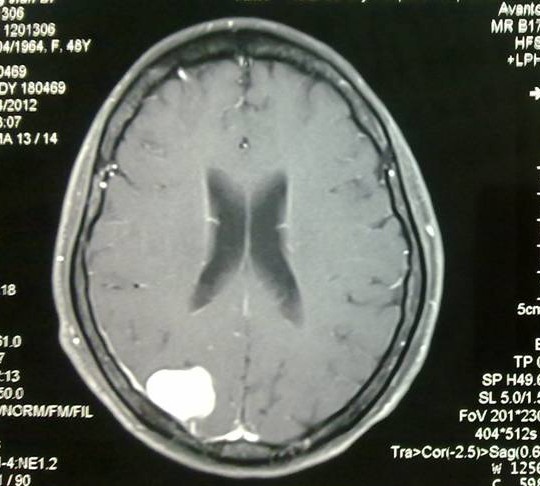

術(shù)前MRI增強(qiáng)成像,腫瘤位于右頂葉,與矢狀竇較為接近,而術(shù)中實際情況是有一部分腫瘤組織直接貼在矢狀竇壁上,手術(shù)難度比術(shù)前預(yù)計的更大。